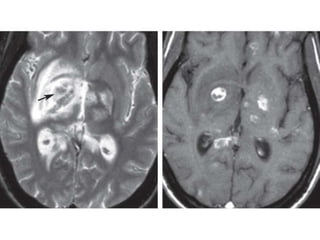

•   Zonas focales asimetricas periventricular y subcortical.

•   Pueden ser bilaterales, múltiples o únicas

•   Efecto de masa y hemorragia no es común

•   Gmente no hay mejoria de lesiones.

Zonas focales asimetricas periventricular y subcortical. • Pueden ser bilaterales, múltiples o únicas • Efecto de masa y hemorragia no es común • Gmente no hay mejoria de lesiones.